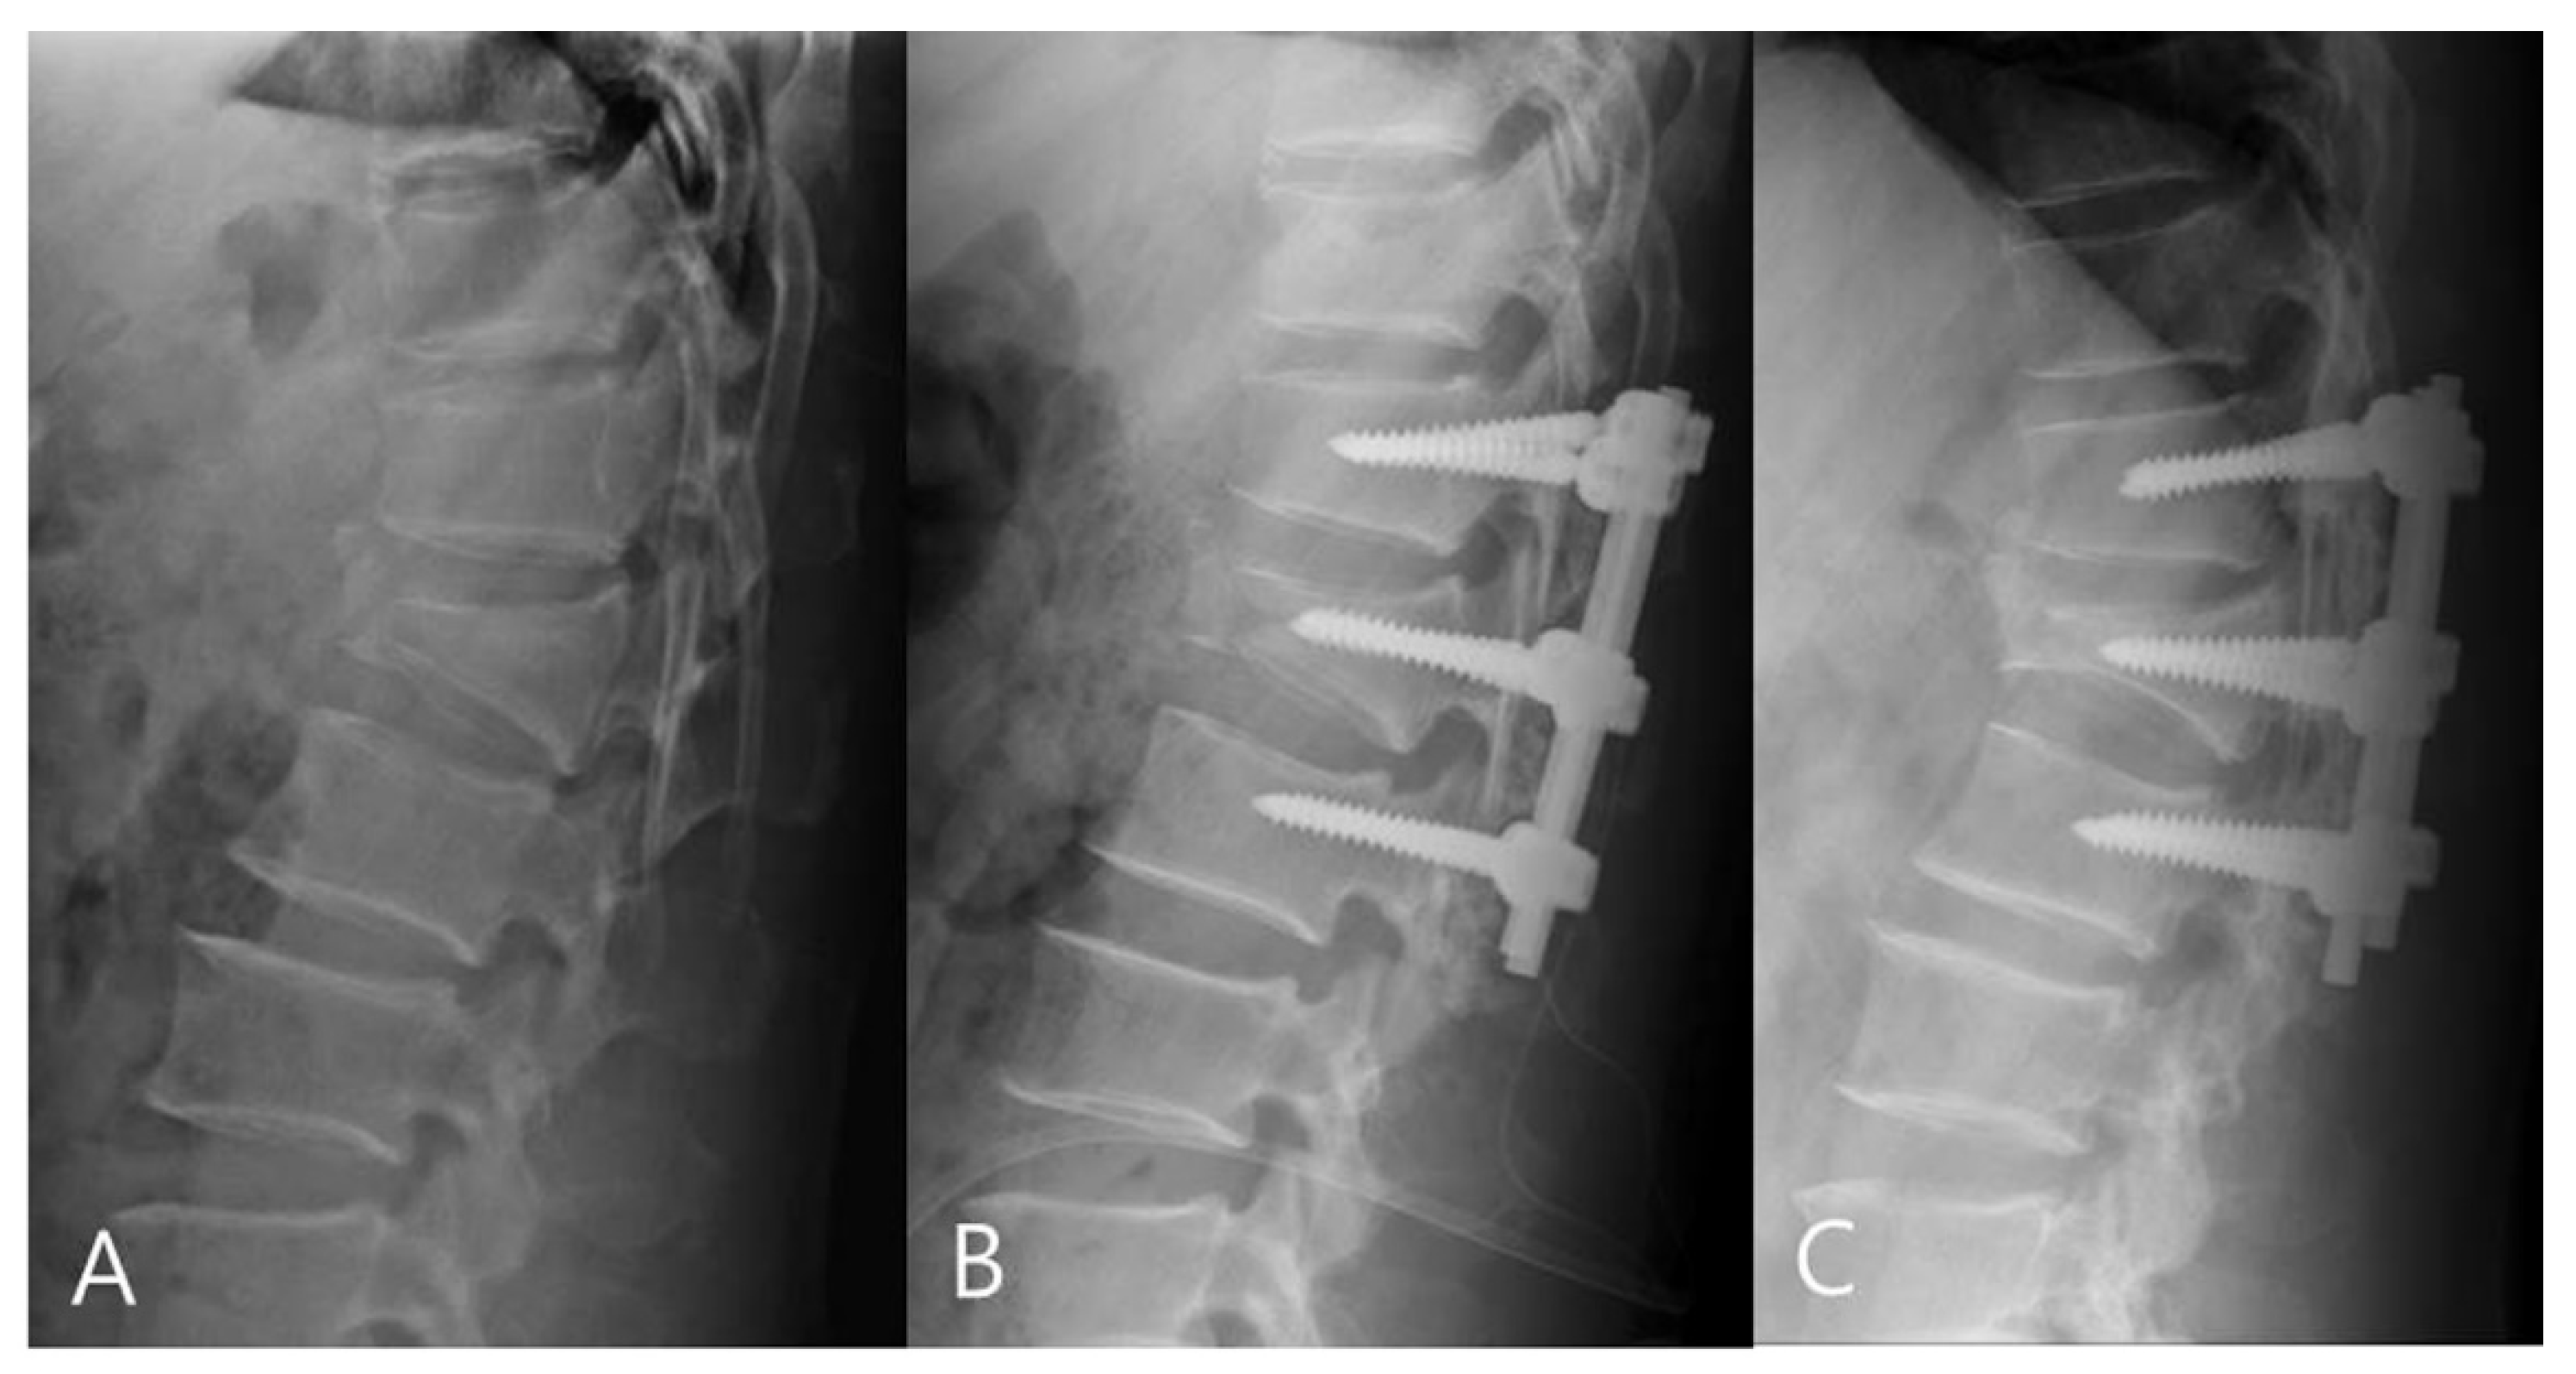

2.2. Operative Technique

3.1. Radiographic Outcomes

3.2. Clinical Outcomes